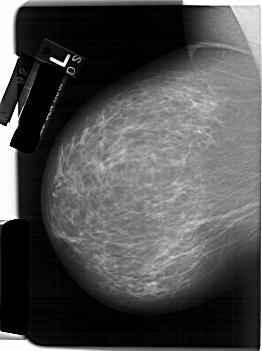

A_1232_1.RIGHT_MLO

RIGHT_MLO LINES 6196 PIXELS_PER_LINE 4336 BITS_PER_PIXEL 12 RESOLUTION 43.5 OVERLAY

FILE: A_1232_1.RIGHT_MLO.OVERLAY

TOTAL_ABNORMALITIES 1

ABNORMALITY 1

LESION_TYPE CALCIFICATION TYPE PLEOMORPHIC DISTRIBUTION LINEAR

ASSESSMENT 4

SUBTLETY 3

PATHOLOGY MALIGNANT

TOTAL_OUTLINES 1